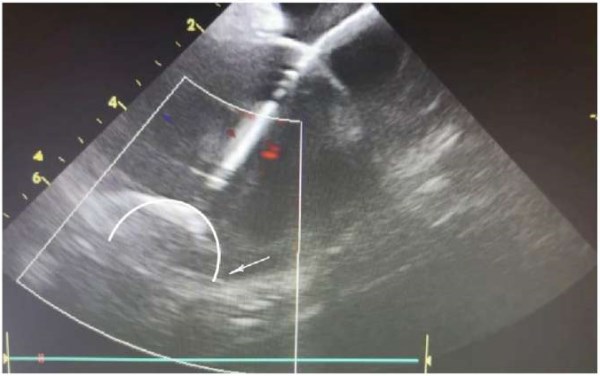

Рис. 9. После изменения положения баллона под контролем внутрисердечной эхокардиографии «leak» по нижнему краю прекратился.